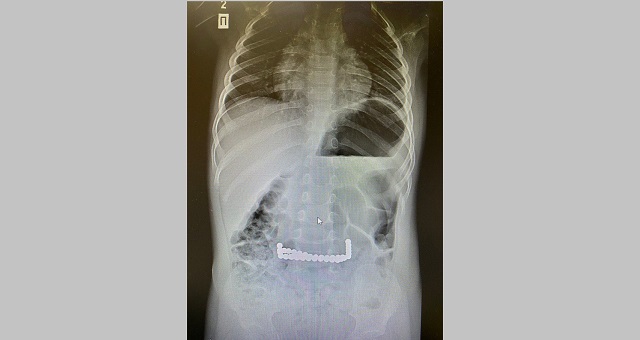

В первом случае школьник случайно проглотил швейную иглу, которая через пищевод попала в желудок. Инородный предмет успешно достали эндоскопическим путем, ребенок в это время находился под наркозом.

Во втором случае мальчик проглотил иголку от циркуля. Ему была проведена аналогичная операция. По словам врача хирурга КДМЦ Ларисы Сираевой, сложность подобных операций заключается в том, что иглу очень сложно взять по оси, чтобы не повредить пищевод.

Кроме того, игла может впиться и проткнуть стенки пищевода, желудка или кишечника. Это, в свою очередь, может привести к серьезному воспалительному процессу. Потеря времени может грозить ребенку жизни. Поэтому очень важно в первые часы приехать в стационар для извлечения инородного тела.

Фото: пресс-служба КДМЦ